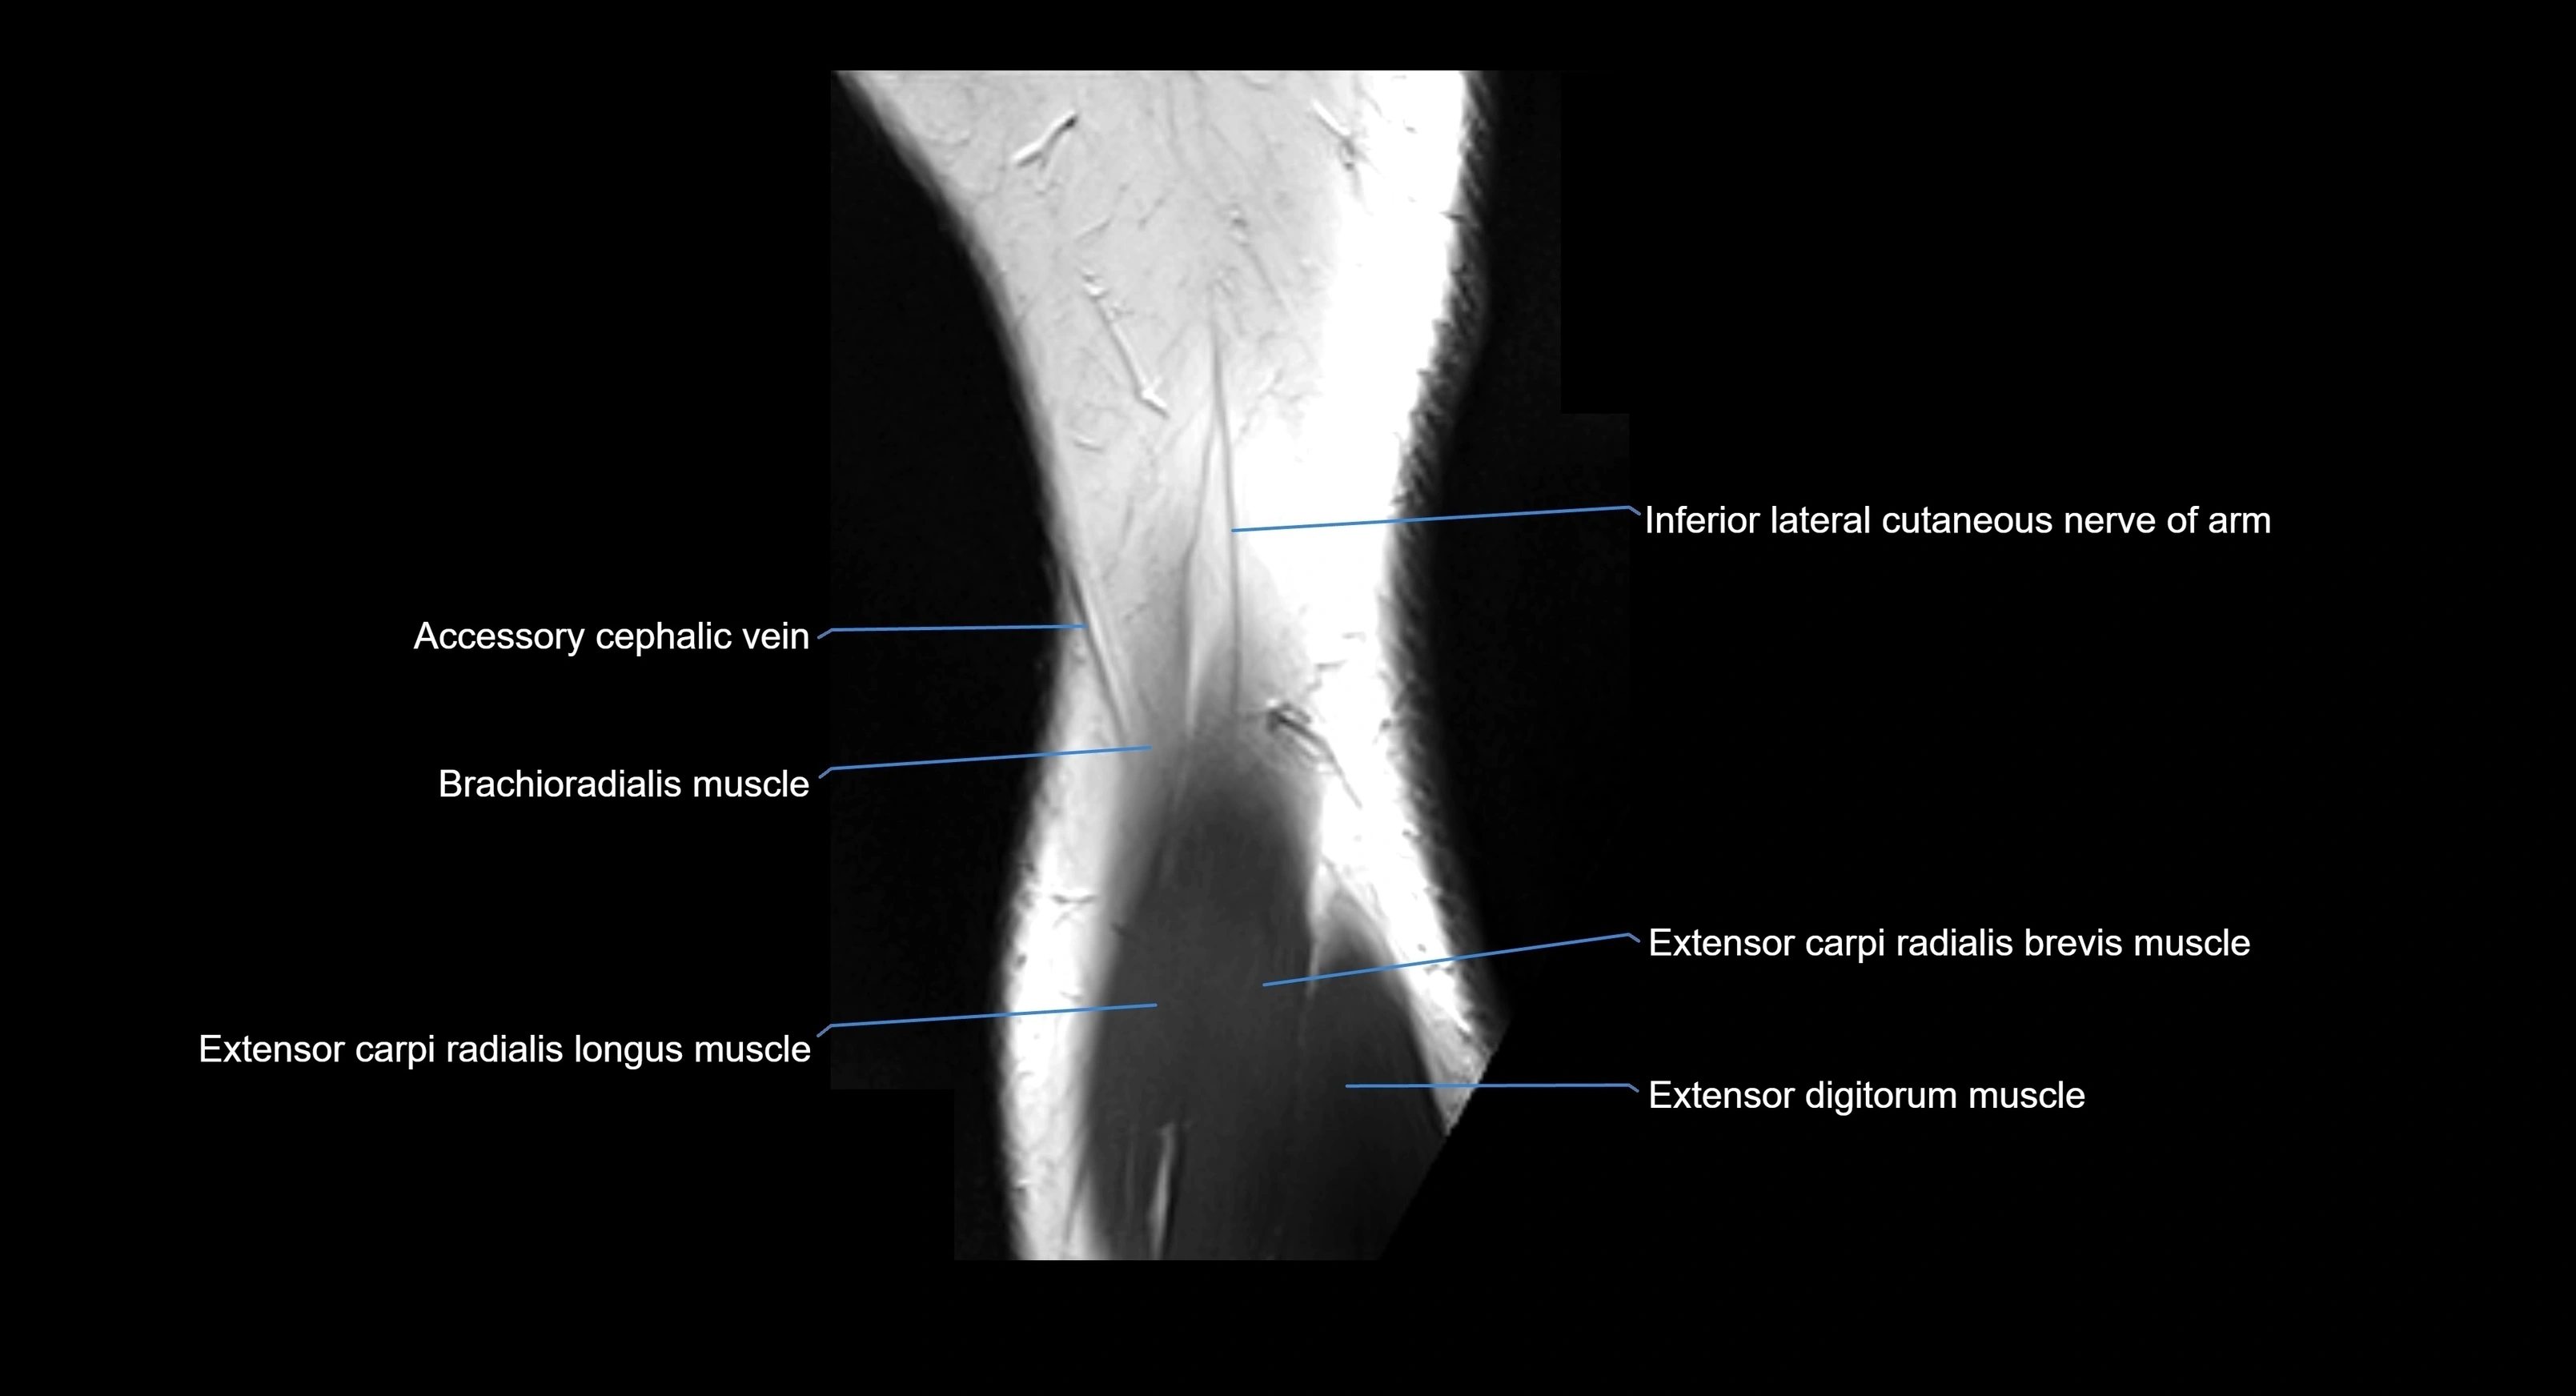

MRI image

image